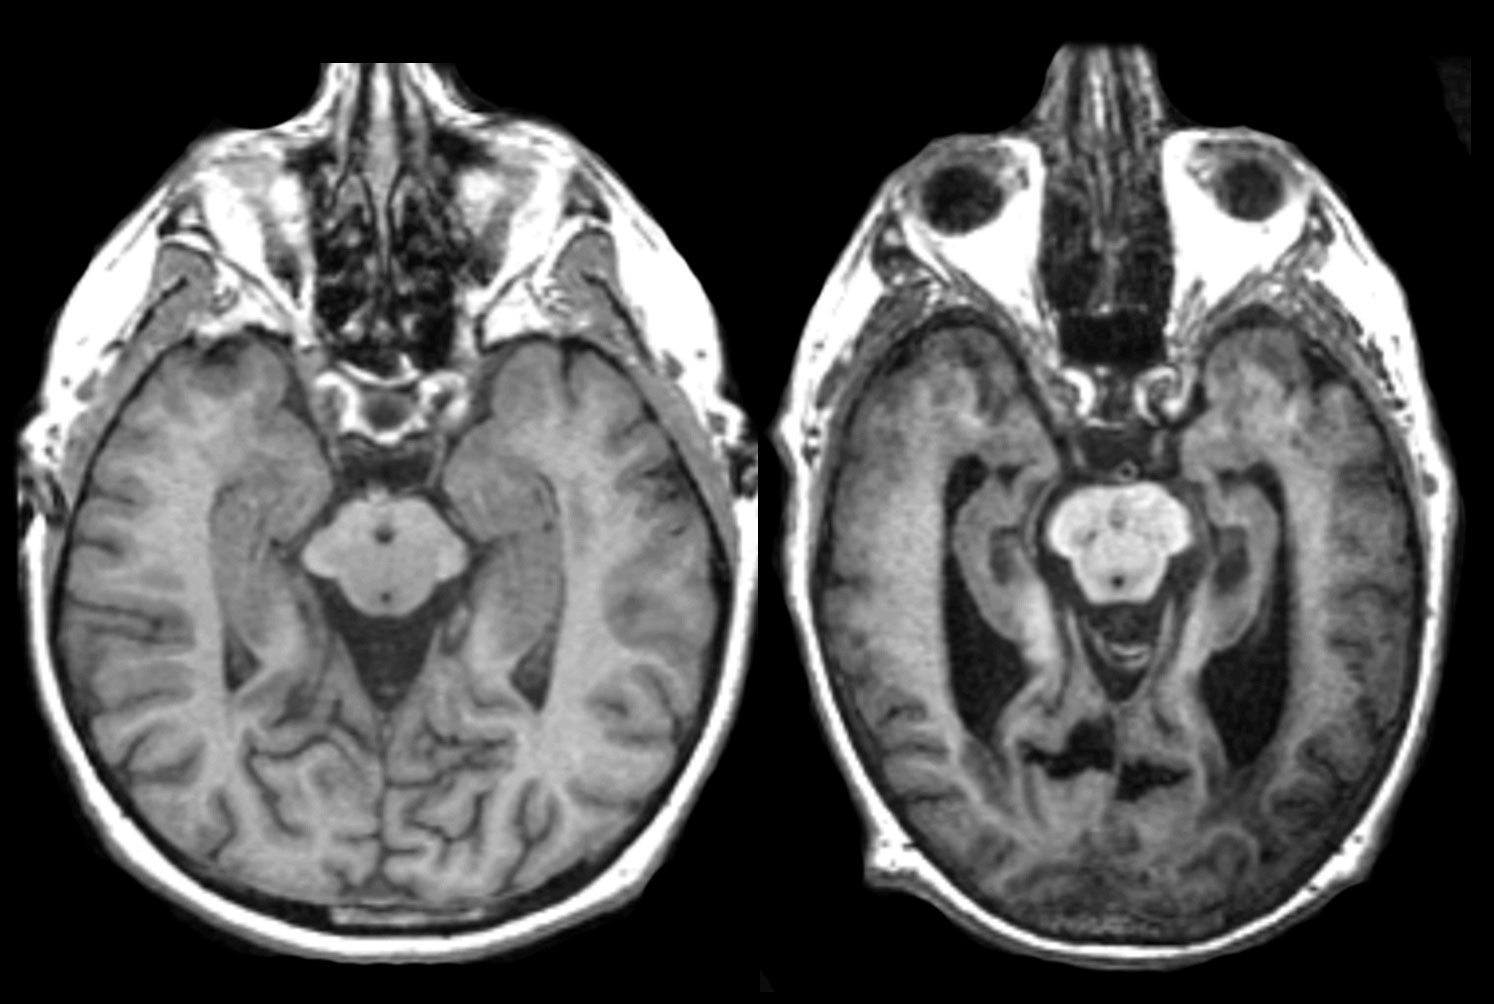

Les premiers symptômes commencent dans le cerveau à un niveau microscopique, et seront reflétés par des pertes de mémoire. Le cerveau est composé de millions de neurones connectés les uns aux autres et qui communiquent entre eux. Il existe des groupes de cellules spécialisées pour aider et entretenir les autres cellules, d’autres qui contribuent à la mémoire, à l’apprentissage, etc… La zone du cerveau qui est principalement chargée de la mémoire se nomme l’hippocampe.

Les recherches démontrent que la maladie d’Alzheimer produit une détérioration de certaines parties de ces cellules qui contribuent à la mémoire et à l’apprentissage. Bien qu’il n’y ait toujours pas de certitude sur la provenance exacte du problème, il est certain qu’un mauvais fonctionnement de ces cellules entraîne des conséquences dans divers zones du cerveau, dû aux multiples connections neuronales qui existe dans notre cerveau. Au fur et à mesure que la maladie se propage, les dégâts dans les cellules s’étend et celles-ci cessent de remplir leurs tâches, et généralement meurent. Avec le temps, le cerveau se “rétrécie”, ce qui affecte quasiment toutes ses fonctions.